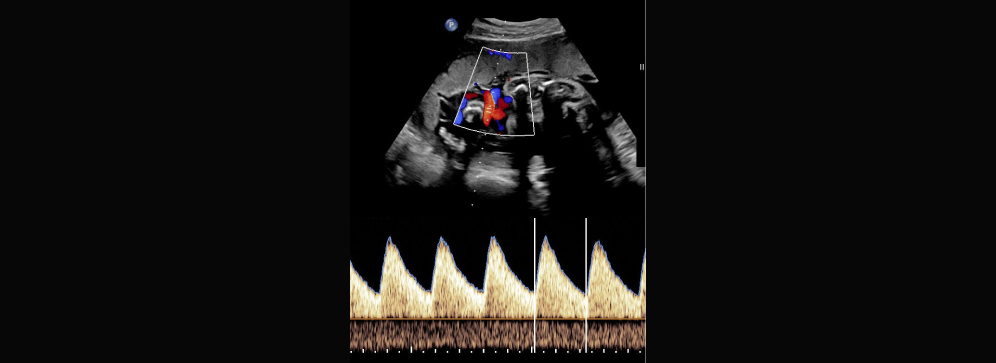

The fetal Doppler scan uses ultrasound waves to detect and measure blood flow in various parts of the fetus and placenta. A special probe is gently moved over the mother’s abdomen after applying a clear gel. The machine then processes these sound waves and displays them as graphs or colour-coded images, allowing doctors to assess circulation patterns in real time.

At Insight Diagnostics and Labs, we use advanced colour Doppler technology for better visualisation. This allows our radiologists to detect even subtle changes in blood flow, which can be crucial in preventing complications. The scan is completely painless and typically takes 20–30 minutes, depending on the baby’s position and cooperation during the scan.

• Displays results as graphs and colour images

After the scan, our radiologist will explain the findings in simple, non-technical terms. The results typically indicate whether blood flow is normal or if there are signs of restriction, which could suggest a need for closer monitoring or intervention. Graphs and images from the scan are included in your report for your doctor’s reference.

• Detailed graphs and colour images provided